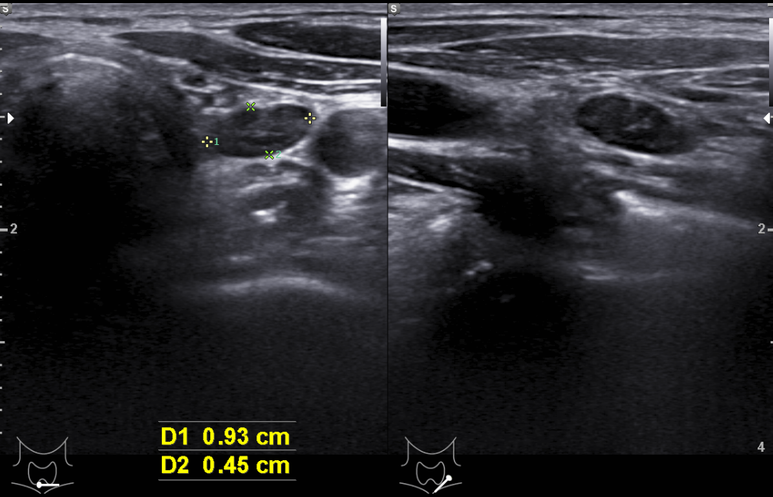

결절의 크기가 증가함

hilum의 혈관이 잘 관찰됨

세침검사 시행함.

bx결과

; [ Cytologic Diagnosis ]Thyroid, left lower, (1.48x0.55cm), aspiration cytology;Sheet of lymphocytic cells(favor hyperplastic lymphoid tissue) - 반응성 변화에 가깝다.

진행하는 갑상선염에 의한 림프절의 크기 변화?